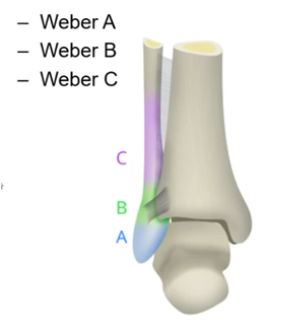

How are distal fibular fractures classified?

Weber’s classification

Based on location in relation to the syndesmosis between fibular and tibia

What is meant by a Weber A fracture?

Weber A - Inferior to syndesmosis

What is meant by a Weber B fracture?

Weber B - In line with syndesmosis

What is meant by a Weber C fracture?

Weber C - Superior to syndesmosis